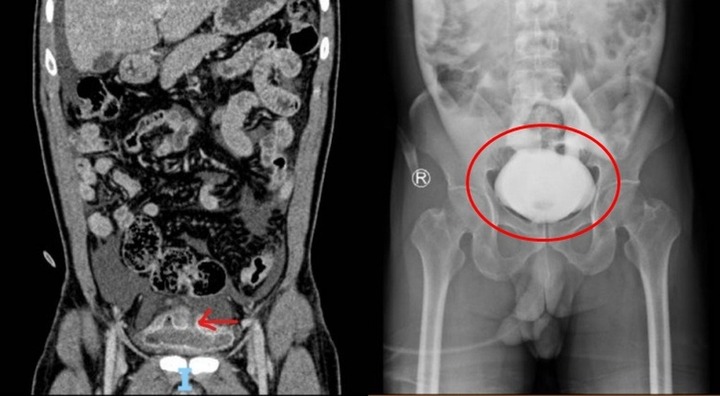

Các bác sĩ nhất trí cho rằng người đàn ông đã không ăn đoạn dây sạc điện thoại như anh ta cam đoan mà đã đưa nó vào cơ thể qua đường phía dưới kiểu "tự sướng".